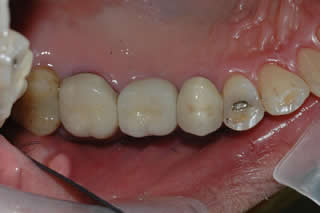

Implant Crown:

The one 3rd from the left is the implant crown. The good thing about this implant crown is that there will be no recurrent decay underneath of implant crown as compared to the regular tooth crown.